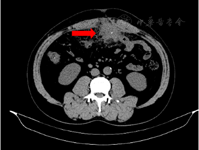

患者,男性,55岁,因"反复腹痛伴低热2个月余,加重1周"于2016年10月9日入院。患者于半年前因胆总管结石、胆囊结石先后行内镜下逆行胰胆管造影+括约肌切开术、腹腔镜胆囊切除术(Laparoscopic cholecystectomy, LC),术后恢复良好出院。2个多月前开始感觉中腹部疼痛,脐周偏左明显,伴有低热38 ℃左右,经抗感染等对症支持治疗后减轻,而后反复发作,曾在多家医院诊治,病情反复。入院查体:体温37.9 ℃,腹平软,脐下1.0 cm、剑突下1.0 cm、右锁中线肋缘下0.5 cm、右锁中线平脐水平0.5 cm手术切口均愈合良好,脐周皮肤稍发红,未见皮疹、胃肠型及蠕动波,脐周偏左压痛明显,无反跳痛、肌紧张,脐周偏左可触及大小约4 cm×5 cm包块,质地硬,移动度可,边界清楚,明显触痛。化验示肝功能、肾功能、电解质、大小便常规、凝血功能、降钙素原均未见异常。血常规示:白细胞16.07×109 /L,中性粒细胞比率85.1%,腹部增强CT提示中腹部脐水平团块状密度增高伴条状致密影,大小约2.7 cm×4.1 cm,炎性包块可能性大,与周围肠管粘连(见封四,图1)。经胃肠外科会诊后,术前诊断考虑中腹部占位:炎性包块可能性大,胆囊切除术后腹腔脓肿待排。鉴于患者反复发热、腹痛,保守治疗后病情反复,建议抗感染控制急性炎症后予以剖腹探查以明确诊断并彻底清创引流。患者同意手术治疗,经充分抗感染治疗后患者未发热,血常规示:白细胞8.76×109 /L,中性粒细胞比率69.9%,脐周疼痛症状得到缓解。